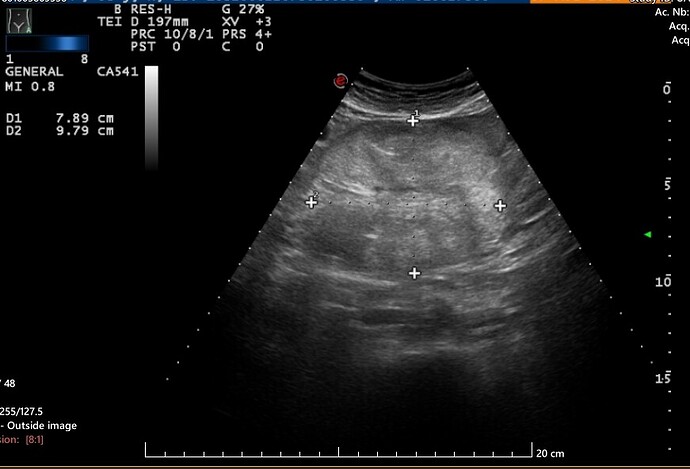

I had an ultrasound of the urinary tract last year and the liver and kidneys. on the scan an ‘incidental’ well defined 9cm hypoechoic ‘mass’ showed up on the final report with minimal vascularity on doppler interrogation at the central abdomen (above umbilicus region).

A week later I had a Abdomen CT Scan with contrast and the final report of that was that there was no abnormality found in the central abdomen and that the ultrasound finding was probably an artefact of the ultrasound imaging - for that reason they will not send me for a follow up with either ultrasound/CT or mri again because they are of the mindset that it was just an artefact and that was that and that there is nothing there even though i am still getting abdomen pains, in that area (just above umbilical cord area) - I cannot also get my head around how something so large at 9cm with a well defined edge and vascularity can be put down to an artefact.

Other investigations I am doing on the internet is pointing to suggests there is something showing up and that it is a mesenteric or retroperitoneal mass when I have sent images of the mass outlined on the ultrasound , and CT slides - what are the changes that maybe the CT radiographer has missed it on the CT slides? - at the moment the doctors have taken the decision that the CT radiographer result is final and that nothing is found and does not warrant another scan.